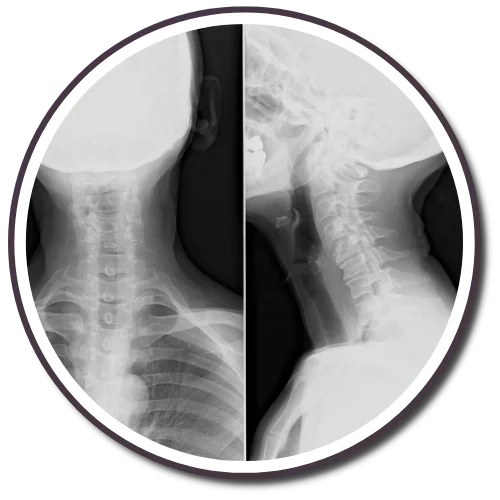

The Gonstead Technique relies on five essential components: Visualization, Instrumentation, Palpation, X-Ray, and patient symptoms. By integrating these elements, we can pinpoint the precise location that requires adjustment. When all these factors align, we can provide the patient with a specific and effective adjustment. Specificity is the key, as Dr. Gonstead emphasized that three adjustments on the wrong vertebral segment could lead to a Subluxation, highlighting the importance of precision.

Dr. Gonstead's Level Disc Theory asserts that "anatomically and physiologically normal discs promote optimum vertebral alignment." This is evidenced when the vertical height of a vertebral couple is uniform around 360 degrees, with the vertebral bodies properly aligned. This alignment, known as "Parallel Discs," ensures even weight distribution, adequate nutrient flow, and optimal joint function and movement within the spine.